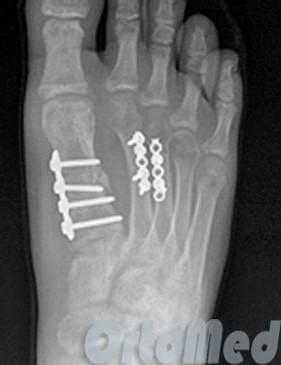

Открытая репозиция перелома

Открытая репозиция при переломе плюсневой кости стопы, накостный остеосинтез пластиной и винтами. Операция включает в себя хирургический разрез, доступ к сломанной плюсневой кости аккуратно отводя сухожилия, сосуды и нервы, мобилизацию костных отломков, устранение смещения и фиксация в правильном положении.

Гипсовая иммобилизация не проводится, так как металлоконструкция, фиксирует отломки.

Разрешается ходьба с опорой на пяточную область в течение месяца.